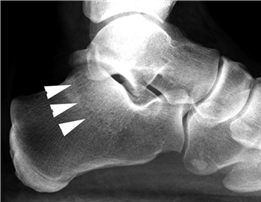

The sesamoid complex, embedded within the flexor hallucis brevis (FHB) tendons, acts as a fulcrum to increase the mechanical advantage of the intrinsic flexors. The tibial (medial) and fibular (lateral) sesamoids articulate with the plantar facets of the first metatarsal head, separated by the crista. In severe hallux valgus, the metatarsal head pronates and drifts medially off the sesamoid apparatus, leading to erosion of the crista and intractable pain. Surgical realignment must restore this delicate sesamoid-metatarsal relationship to ensure long-term success and prevent recurrence.

Weight-bearing anteroposterior (AP), lateral, and sesamoid axial radiographs are mandatory. On the AP view, the surgeon measures the Hallux Valgus Angle (HVA, normal < 15°), the Intermetatarsal Angle (IMA, normal < 9°), and the Distal Metatarsal Articular Angle (DMAA). The lateral view is scrutinized for Meary's angle (talo-first metatarsal angle) to identify midfoot collapse, as well as the presence of dorsal osteophytes indicative of hallux rigidus. The sesamoid axial view is critical for assessing the degree of sesamoid subluxation and the integrity of the crista.

Clinical & Radiographic Imaging Archive